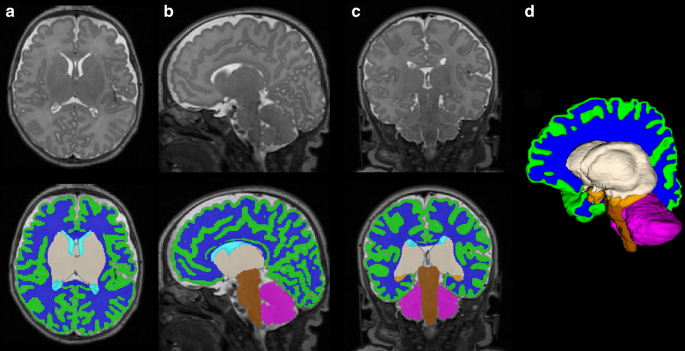

Volumetric segmentation was performed on coronal T2 Cube 3D images using a validated automated algorithm via the Draw-EM (Developing brain Region Annotation With Expectation-Maximization) package,40 with subsequent manual inspection and correction as needed by two investigators blinded to enteral nutrition type (KO and KK).37 Tissue-specific brain volumes were obtained for the cortical and deep gray matter, white matter, amygdala-hippocampus, cerebellum, and brainstem; total brain volume was calculated as the sum of all tissue-specific brain volumes for each infant (Fig. 1). DTI data were preprocessed based on a previously published pipeline, with cubic regions of interest (21-49mm3) manually placed by two investigators blinded to enteral nutrition type (KO and KK) using predefined anatomical landmarks in the corpus callosum (genu and splenium), posterior limb of internal capsule, and brainstem (pons).41 Fractional anisotropy (FA) and mean diffusivity (MD) values, measuring directionality and net diffusion of water molecules, respectively, were calculated for each region of interest. Inter- and intra-rater reliability measures for manually corrected MRI brain volumes and DTI region of interest placement were calculated based on a randomly selected subset of 35 patients using the intraclass correlation coefficient.

Brain volumes

Term-equivalent volumetric data were available for all 152 infants (67 mother’s own milk, 44 donor human milk, 41 preterm formula). Intra- and inter-rater reliability intraclass correlation coefficients for MRI volumetric segmentation were 0.96 and 0.95, respectively. Total and tissue-specific brain volumes were lower in infants receiving donor human milk and preterm formula compared to mother’s own milk (Table 2). There were no significant differences in brain volumes between infants receiving donor human milk and mother’s own milk after adjusting for gestational age at birth and postmenstrual age at MRI. A sensitivity analysis did not reveal any significant differences in brain volumes between infants who received >70% cumulative enteral nutrition from donor human milk (n = 17) compared to mother’s own milk (n = 62).

Infants receiving preterm formula demonstrated significantly lower brain volumes compared to mother’s own milk in the total brain (308.6 ± 55.2 vs. 324.5 ± 46.7 cm3, β = –17.2, p = 0.016), deep gray matter (23.1 ± 3.7 vs. 24.2 ± 2.7 cm3, β = –1.2, p = 0.024) and brainstem (5.1 ± 0.6 vs. 5.5 ± 0.8 cm3, β = –0.4, p = 0.002); volumes were also lower in the cortical gray matter (121.5 ± 27.9 vs. 128.1 ± 23.6 cm3, β = –7.0, p = 0.028) and white matter (137 ± 22.7 vs. 144.6 ± 17.9 cm3, β = –7.6, p = 0.026) compared to mother’s own milk. Incorporation of SVI into multivariate models yielded similar results except that the differences in cortical gray matter were more pronounced between preterm formula and maternal milk-fed infants (β = –7.4, p = 0.025), whereas differences in deep gray matter volumes (β = –1.2, p = 0.027) were no longer statistically significant (Supplementary Table S1). Adjusting for systemic steroid exposure did not significantly affect the relationship between preterm formula and maternal milk-fed infants in the brainstem (β = –0.3, p = 0.005) but attenuated the differences in total brain (β = –15.9, p = 0.03) and deep gray matter (β = –1.1, p = 0.04) volumes. Infant sex revealed no significant effects. In post-hoc analyses, brain volumes did not significantly differ between preterm formula compared to donor milk-fed infants (Table 5).